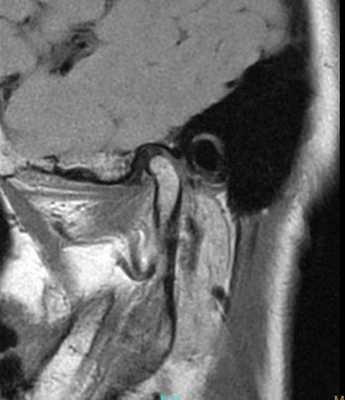

69-летняя пациентка с основными жалобами на боли в проекции челюсти, ограниченное открытие полости рта и невозможностью выдвинуть челюсть вперед обратилась за стоматологической помощью. Со слов пациентки ее симптомы начали развиваться около 6 месяцев назад: именно тогда она заметила, что ей трудно выдвигать челюсть вперед, чтобы посвистеть к своей собаки. По данным анамнеза на протяжении около 50 лет больная отмечала «выскакивание» и «пощелкивание» челюсти с левой стороны, и данные симптомы прекратились приблизительно в то время, когда ей стало трудно выдвигать нижнюю челюсть вперед. В ходе клинического осмотра было обнаружено, что максимальная величина межрезцового расстояния составляла 35 мм, при этом в ходе максимального открытия полости рта челюсть несколько смещалась влево. После массажа и растяжения левой жевательной мышцы и сустава снизилась интенсивность болевых ощущений, однако объем движений не увеличился. Таким образом был поставлен диагноз левостороннего смещения суставного диска без сопровождающейся редукции ВНЧС. Пациентка была направлена на магнитно-резонансную томографию (МРТ), и для исследования локализации и состояния диска при открытом и закрытом рте. Данные МРТ позволили установить, что с левой стороны отмечалось переднее смещение суставного диска в обеих положения, что также подтверждает диагноз смещения без редукции (фото 1-4).

Фото 1. МРТ-скан правого ВНЧС при закрытом состоянии рта: визуализация положения диска.

Фото 2. МРТ-скан правого ВНЧС при открытом состоянии рта: визуализация положения диска.

Фото 3. МРТ-скан левого ВНЧС при закрытом состоянии рта: визуализация переднего смещения диска без редукции.

Фото 4. МРТ-скан левого ВНЧС при закрытом состоянии рта: визуализация переднего смещения диска без редукции.